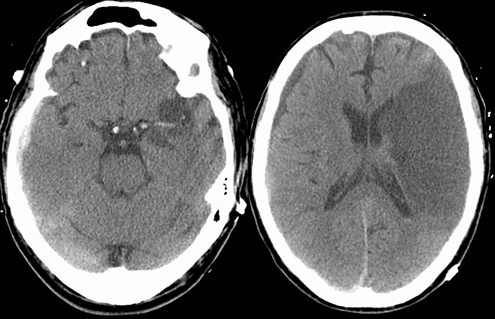

Explainable AI changes this. It shows the logic behind each detection, making it easier for specialists to verify findings. This transparency is especially important for identifying hypodense lesions, which often require careful evaluation due to their subtle appearances across CT & MRI scans in various anatomical regions due to their subtle contrast differences.

Hypodense lesions can be difficult to identify because they share almost visual similarities with the surrounding tissue. Even experienced radiologists may spend significant time reviewing multiple slices of a scan.

AI imaging applications assist in speeding up this process—but only if the accurate data behind them is correct. The strength of any AI model depends on the quality of its training data. When the segmentation is flawed or inconsistent, the model’s output becomes unreliable. This is why high-quality AI segmentation is essential. It ensures every pixel and boundary is segmented with precision. Hypodense lesions can indicate different pathologies depending on the organ, ranging from cerebral infarcts to hepatic cysts, splenic lesions, renal abnormalities, or soft-tissue changes. AI models must be trained on diverse, explainable datasets that reflect this anatomical variability.

We segmented hypodense lesions with pixel-level accuracy, ensuring every boundary and shape is captured correctly, whether the lesion is in the brain, abdomen, or soft tissues.